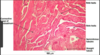

Label the image

seminiferous tubule

label

Testes slide

label

M- myoid cells

IC= interstitial cells

SC= sertoli cells

SG= spermatogonia